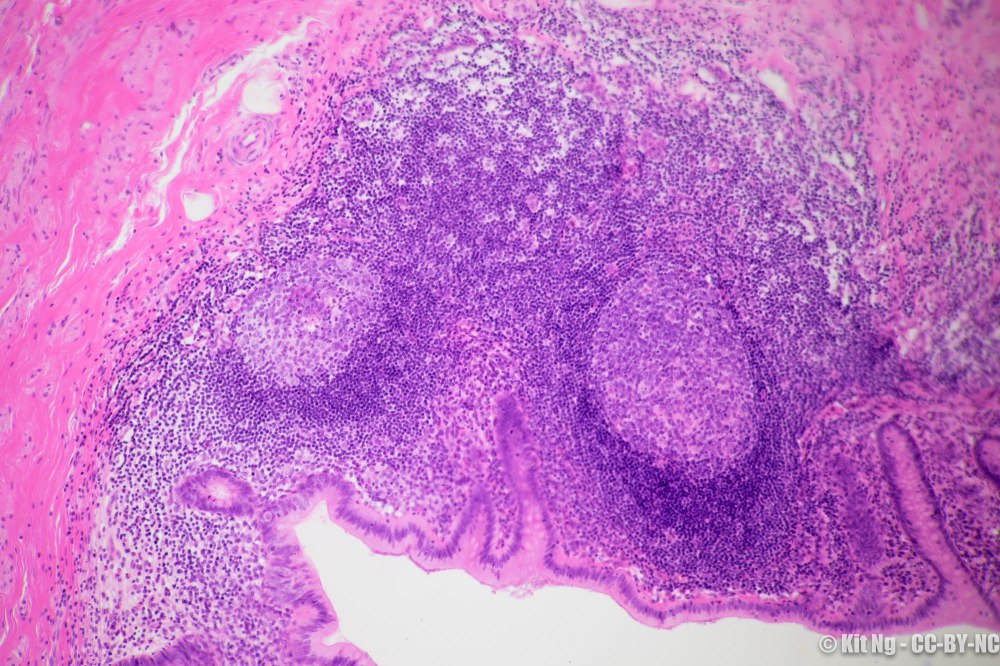

Appendix is a small sac extending from the cecum right off the ileocecal valve. One proposed function of the appendix is that it helps maintain a healthy gut microflora by replenishing the gut with pro-health strains that reside in the appendix.